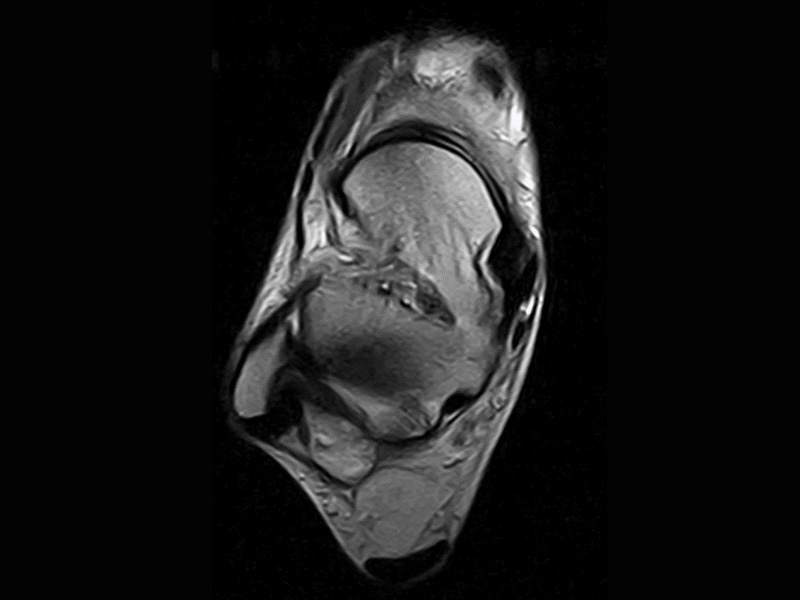

Klinické snímky